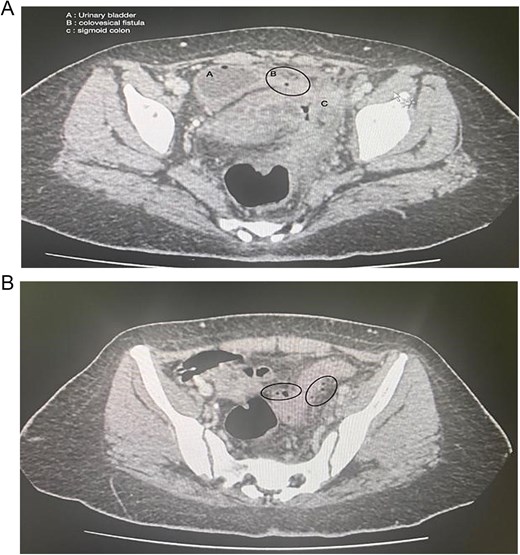

Computed tomography (CT) abdomen and pelvis showed perforated sigmoid diverticulitis, extraluminal collection measuring 3 × 1.8 cm, fistula formation extending to left aspect of urinary bladder dome, and another fistula possibly extending to anterior wall of rectum (Fig. 1).

(A) Axial section of the abdominopelvic CT scan showing the colovesical fistula. (B) Axial section of the abdominopelvic CT scan showing the diverticular disease of the colon.